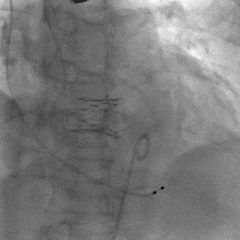

术中影像

左冠造影

左冠狭窄处行PCI处理

PCI后左冠造影,血流通畅

右冠造影

右冠狭窄处行PCI处理

PCI后右冠造影,血流通畅

根部造影,瓣叶活动差

20mm球囊预扩,微腰微漏

输送器过弓

snare辅助下跨瓣

瓣膜初始定位

第一次释放,瓣膜位置偏高,选择回收

第二次瓣膜释放

造影评估,瓣膜位置可

右侧位造影,瓣膜深度可

多角度评估,瓣膜位置可,少量瓣周漏

脱钩后造影,瓣膜无位移,可见瓣周漏

20mm球囊后扩,瓣膜形态改善

后扩后评估,可见少量瓣周漏

最终瓣膜位置稳定